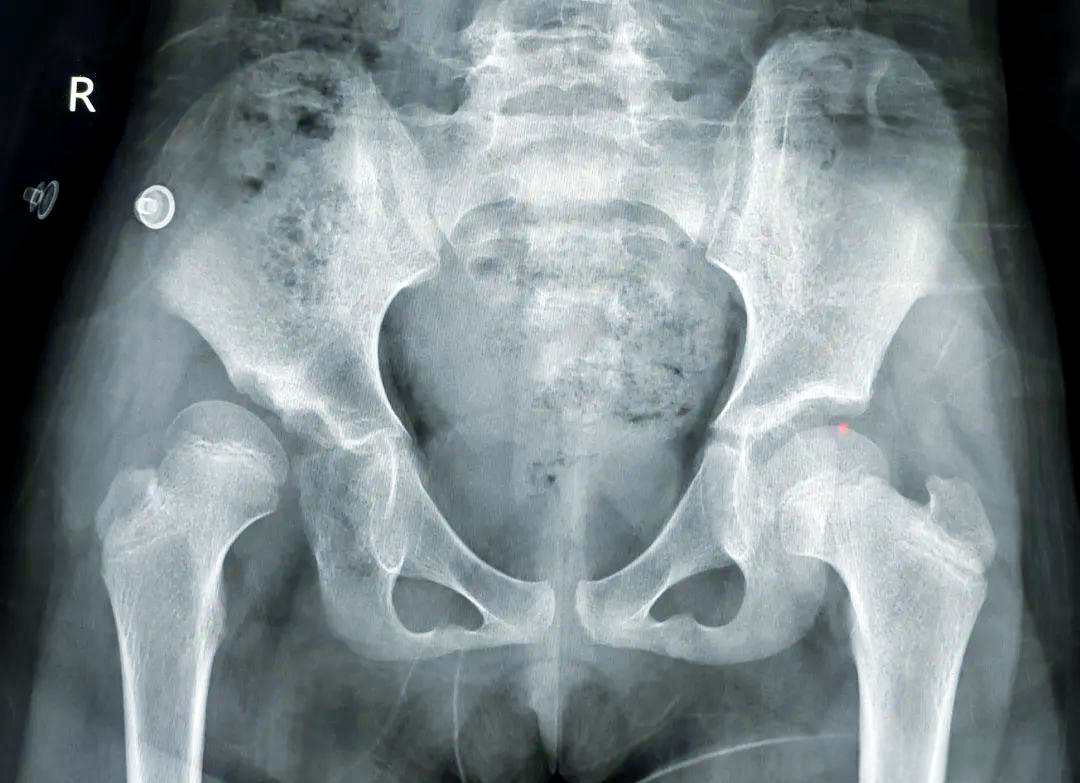

发育性髋关节脱位

6.jpg